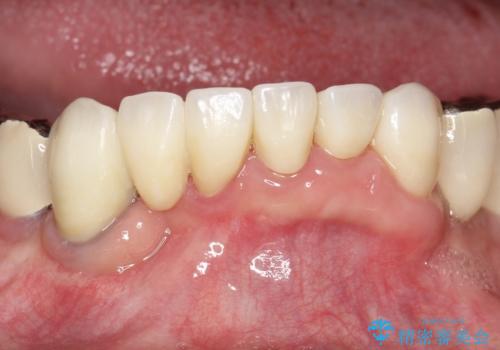

虫歯だらけ、歯周病 崩壊した口腔の再建 フルマウスリコンストラクション

- 歯周外科・インプラント・顕微鏡下根管治療などを含んだ総合的な治療を計画した。

様々な治療手段を高いレベルで同時に併行して行うことが必要でした。

かみ合わせの力が非常に強く、夜間の歯ぎしり・食いしばりもひどかったため、奥歯はメタルオクルーザルの設計でかぶせ物を製作しています。

かぶせ物の種類:PFZ / PFM metal occlusal